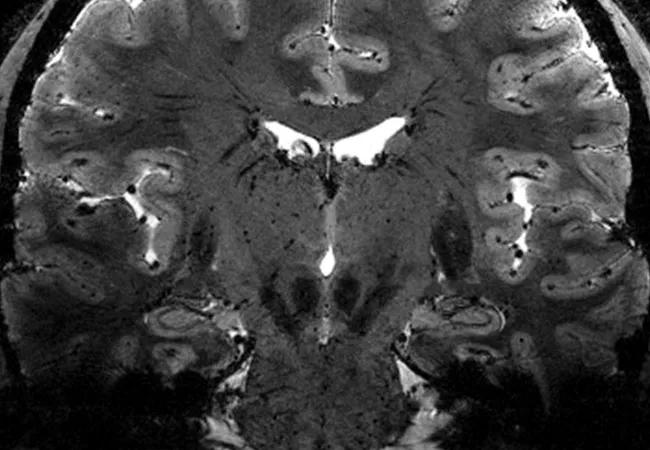

Whole brain and deep gray matter atrophy correlates more strongly with clinical disability than does T2 lesion volume (T2LV) in individuals with multiple sclerosis (MS), according to a Cleveland Clinic platform presentation at the American Academy of Neurology’s 2019 annual meeting on May 7.

The study — led by neuroimmunologist Kedar Mahajan, MD, PhD, in collaboration with staff scientist Kunio Nakamura, PhD, of Cleveland Clinic’s Department of Biomedical Engineering — shines new light on the relevance of deep gray matter atrophy in MS.

Clinical neuroperformance data, demographic and disease characteristics, and patient-reported outcomes were obtained from 997 patients with MS during routine clinical care. MRI brain volumes were analyzed in Dr. Nakamura’s lab for T2LV, whole brain fraction and deep gray matter volumes (thalamus, putamen, caudate and hippocampus). Associations were assessed using Spearman correlation coefficients with significance set at P < 0.001.

There was no association between T2LV and caudate volume. Whole brain volume was identified as the strongest predictor of thalamic volume.